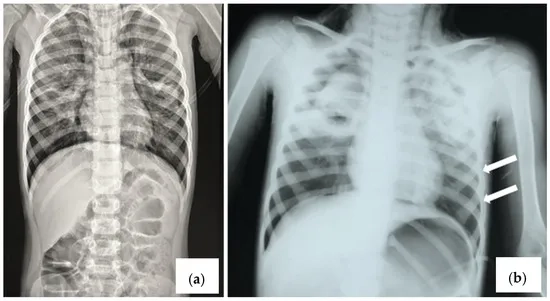

Image of the disease Human Bocavirus Infection